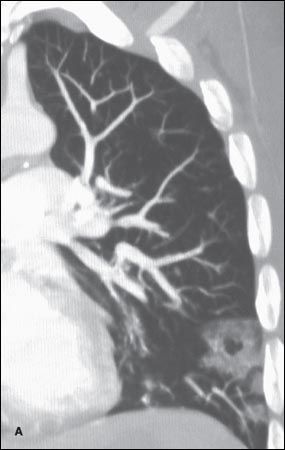

A CT scan of the chest showed subpleural cavitating lung nodules (A and B). Blood cultures grew Staphylococcus aureus, and an echocardiogram confirmed the diagnosis of infective endocarditis.

Septic pulmonary embolism is an uncommon disorder that generally presents with an insidious onset; characteristic features include fever and lung infiltrates associated with an active focus of extrapulmonary infection.1,2 Risk factors are injection drug use, indwelling catheters/ devices, pelvic thrombophlebitis, and suppurative processes in the head and neck.3,4 The embolic blood clot that leads to an infarction and the microorganisms contained in the clot incite a focal abscess.4

The triad of bacteremia, fever, and multiple cavitary pulmonary infiltrates on a chest radiograph should always prompt a search for right-sided infective endocarditis.2,3